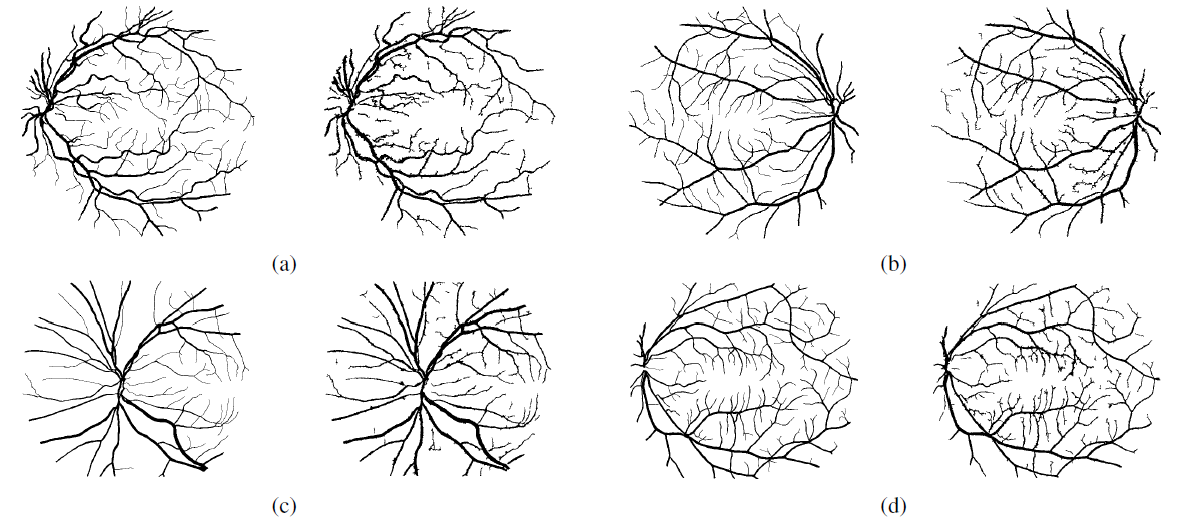

图五 分层更新的示例流程图 本文通过与多个血管分割算法进行比较验证了所提算法的有效性,对比结果如图六所示。实验结果表明,基于分层抠图模型的血管分割算法在两个公开的数据库: DRIVE和STARE上均取得了较好的分割结果。下面我们给出一些血管分割的实例对比结果(如图七所示)。在图七的(a)(b)(c)(d)中,左图均为医生分割的结果,右图为基于算法所分割出的结果。不难看出,基于该算法所得到的分割结果,相比医生分割的结果,提取了更多复杂的特征信息。

图七 血管分割的实例对比示意图 本文以血管分割为例探讨了抠图三分图的自动生成问题,利用图像增强和血管的形状特征实现三分图的自动生成功能,并且提出了一个基于分层抠图模型的算法进行血管分割,扩展了自然图像抠图技术在医学图像领域的应用。该技术有望应用在复杂结构的物体分割、小样本的数据处理等应用场景。在未来的工作中,我们将会继续优化这个算法,提升算法的性能,并与医学领域专家展开合作,尽可能地把算法应用到实际辅助诊断中。 参考文献 [1] Talwar, Powel, and Mithun Das Gupta, “Alpha-matting based retinal vessel extraction,” U.S. Patent 9 675 247, Jun. 13, 2017. [2] Qifeng Chen, Dingzeyu Li, and Chi-Keung Tang, “KNN matting,” in Proc. IEEE Conf. Comput. Vis. Pattern Recognit. (CVPR), Jun. 2012, pp. 869–876. [3] Zhun Fan, Jiewei Lu, Caimin Wei, Han Huang, Xinye Cai and Xinjian Chen*. A hierarchical image matting model for blood vessel segmentation in fundus images[J]. IEEE Transactions on Image Processing, 2019, 28(5): 2367-2377. [4] Han Huang, Yihui Liang*, Xiaowei Yang, Zhifeng Hao. Pixel-level Discrete Multiobjective Sampling for Alpha Matting, IEEE Transactions on Image Processing, [DOI: 10.1109/TIP.2019.2902830]. 文字:卢杰威、刘子钊 实验室负责人:黄翰教授 联系邮箱:hhan@scut.edu.cn 论文页面:http://www2.scut.edu.cn/huanghan/fblw/list.htm |